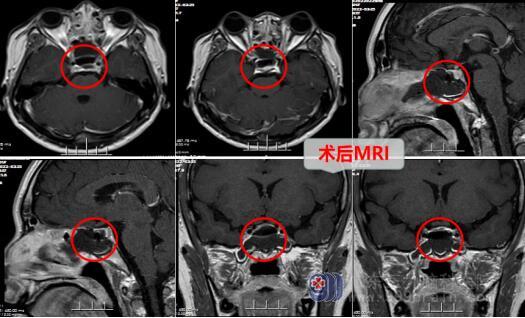

完善各项检查之后,2月18日在全麻下行内镜经鼻碟垂体腺瘤切除术。术后复查MR检查提示:内镜经鼻碟垂体瘤切除术+颅底重建术后改变,复查PRL为0.73ug/L,病理诊断为垂体神经内分泌肿瘤,免疫组化结果为泌乳激素细胞腺瘤。

术后,佳佳恢复很好,于2月25日顺利出院。